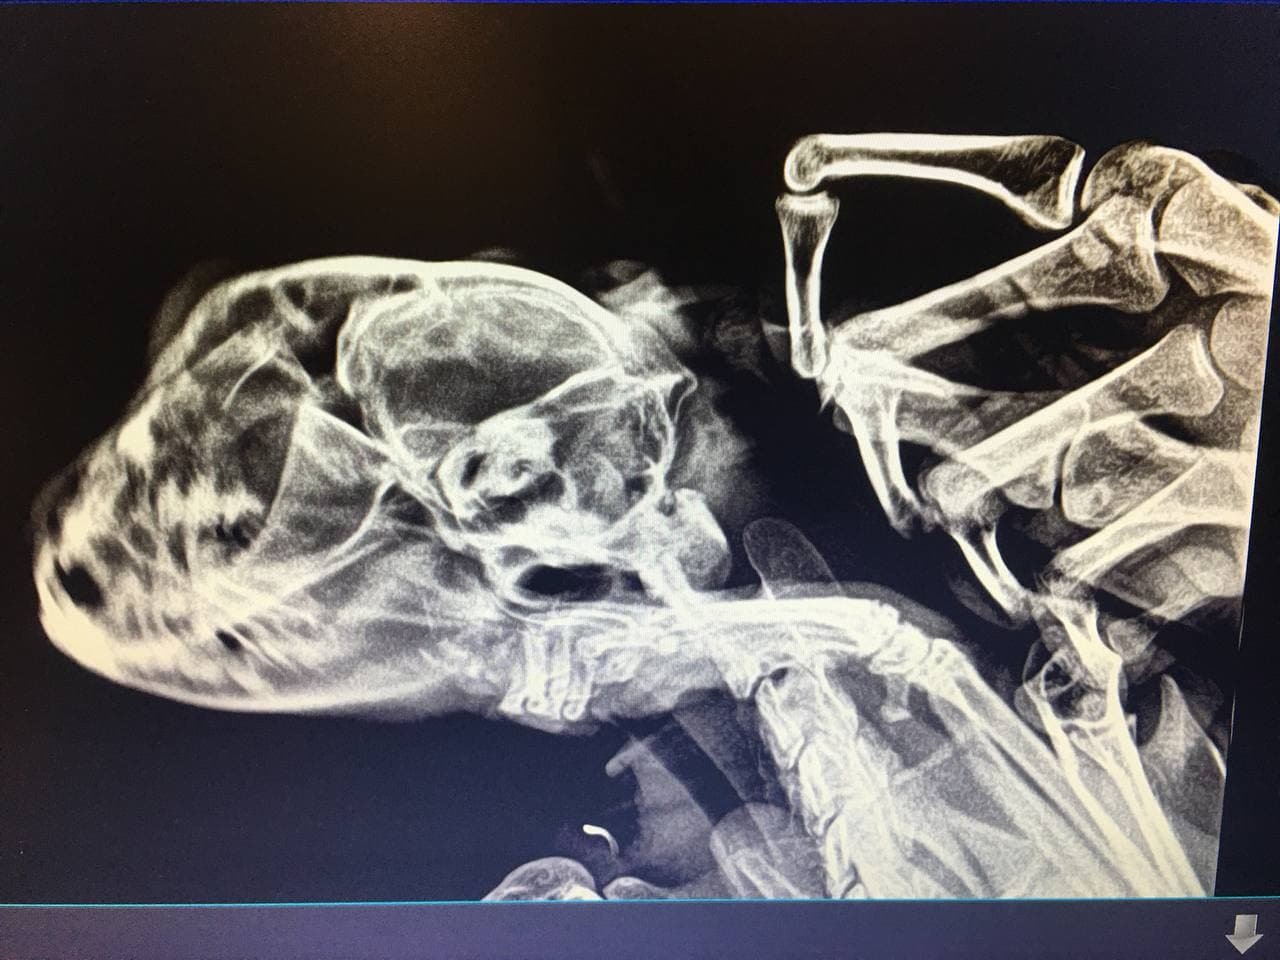

Провожаю второго своего белого кота, прошлый пост лет 5 назад гдето тут лежит.. но на этот раз здорового и полного сил восьми-летнего британца. На утро просыпаюсь  - отказывают ноги, учащается дыхание.  едем в клинику, попутно думаем над диагназом и была идея что кто-то его укусил, т.к. всю ночь спал на рюкзаке который был на природе..

но ситуация оказалась страшнее: тромбоз

сразу сказали что шансов мало, начали колоть кроворазжижающие. На следующий день навещал, поспокойнее стал дышать, лапы с синих приобрели обратно розоватый оттенок, но врач предупредил что тем не менее шансов не много. И спустя еще сутки он ушел.